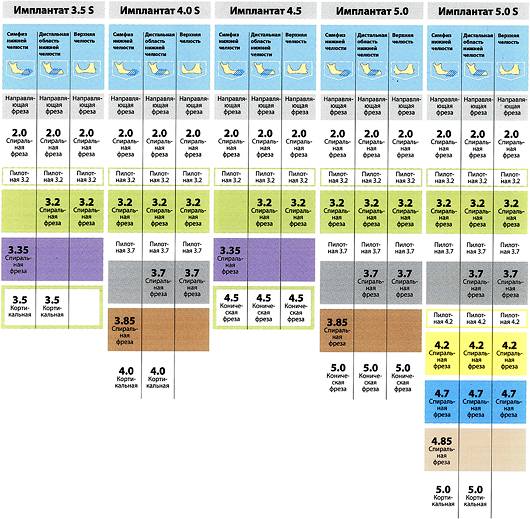

Другая сторона — это сам хирургический протокол. В большинстве имплантационных систем он устроен примерно одинаково: от меньшего размера к большему. Однако, некоторые производители его настолько усложняют, что новичку в нем интуитивно не разобраться. Таков, например, хирургический протокол установки имплантов Astratech:

разумеется, это влечет за собой увеличение количества инструментов и усложнение хирургического набора: